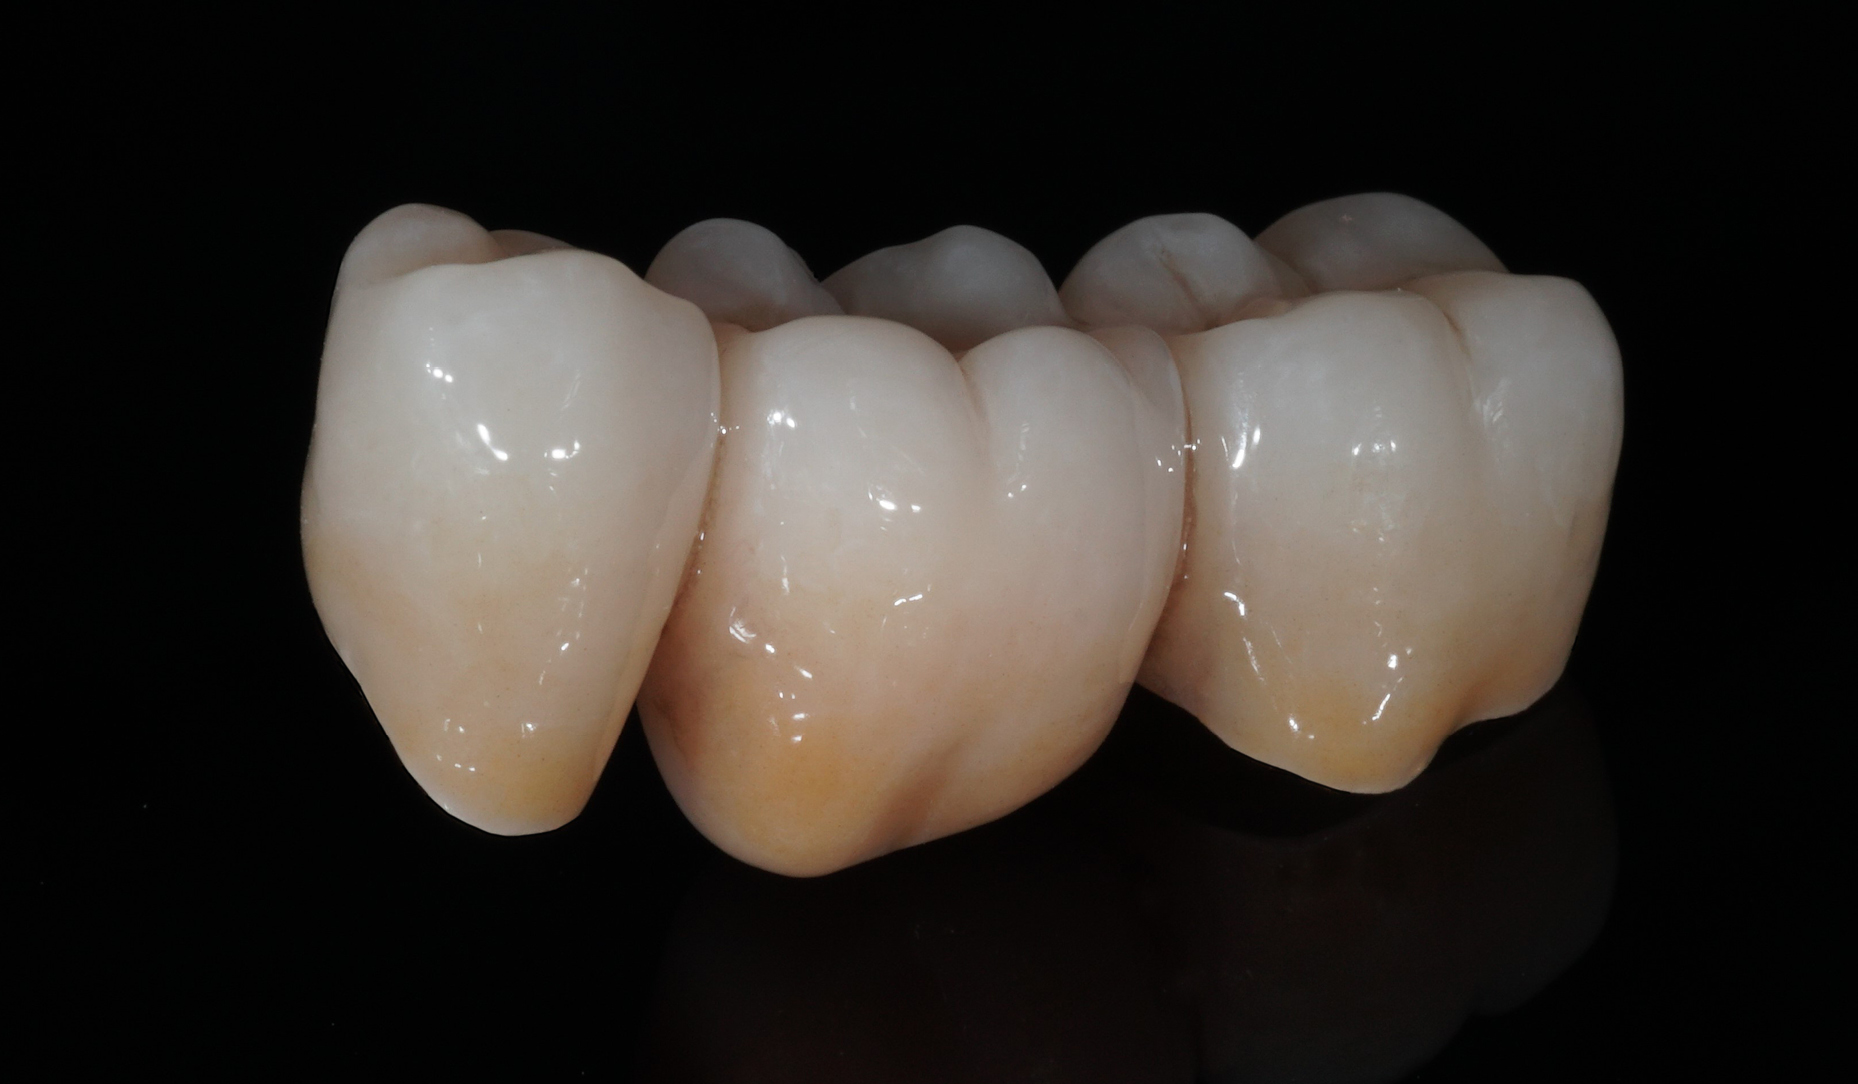

Ryc. 9. Wygląd mostu po indywidualizacji za pomocą płynnej ceramiki CERABIEN™ ZR FC Paste Stain...

Ryc. 10. ... oraz po dwóch wypaleniach glazury.